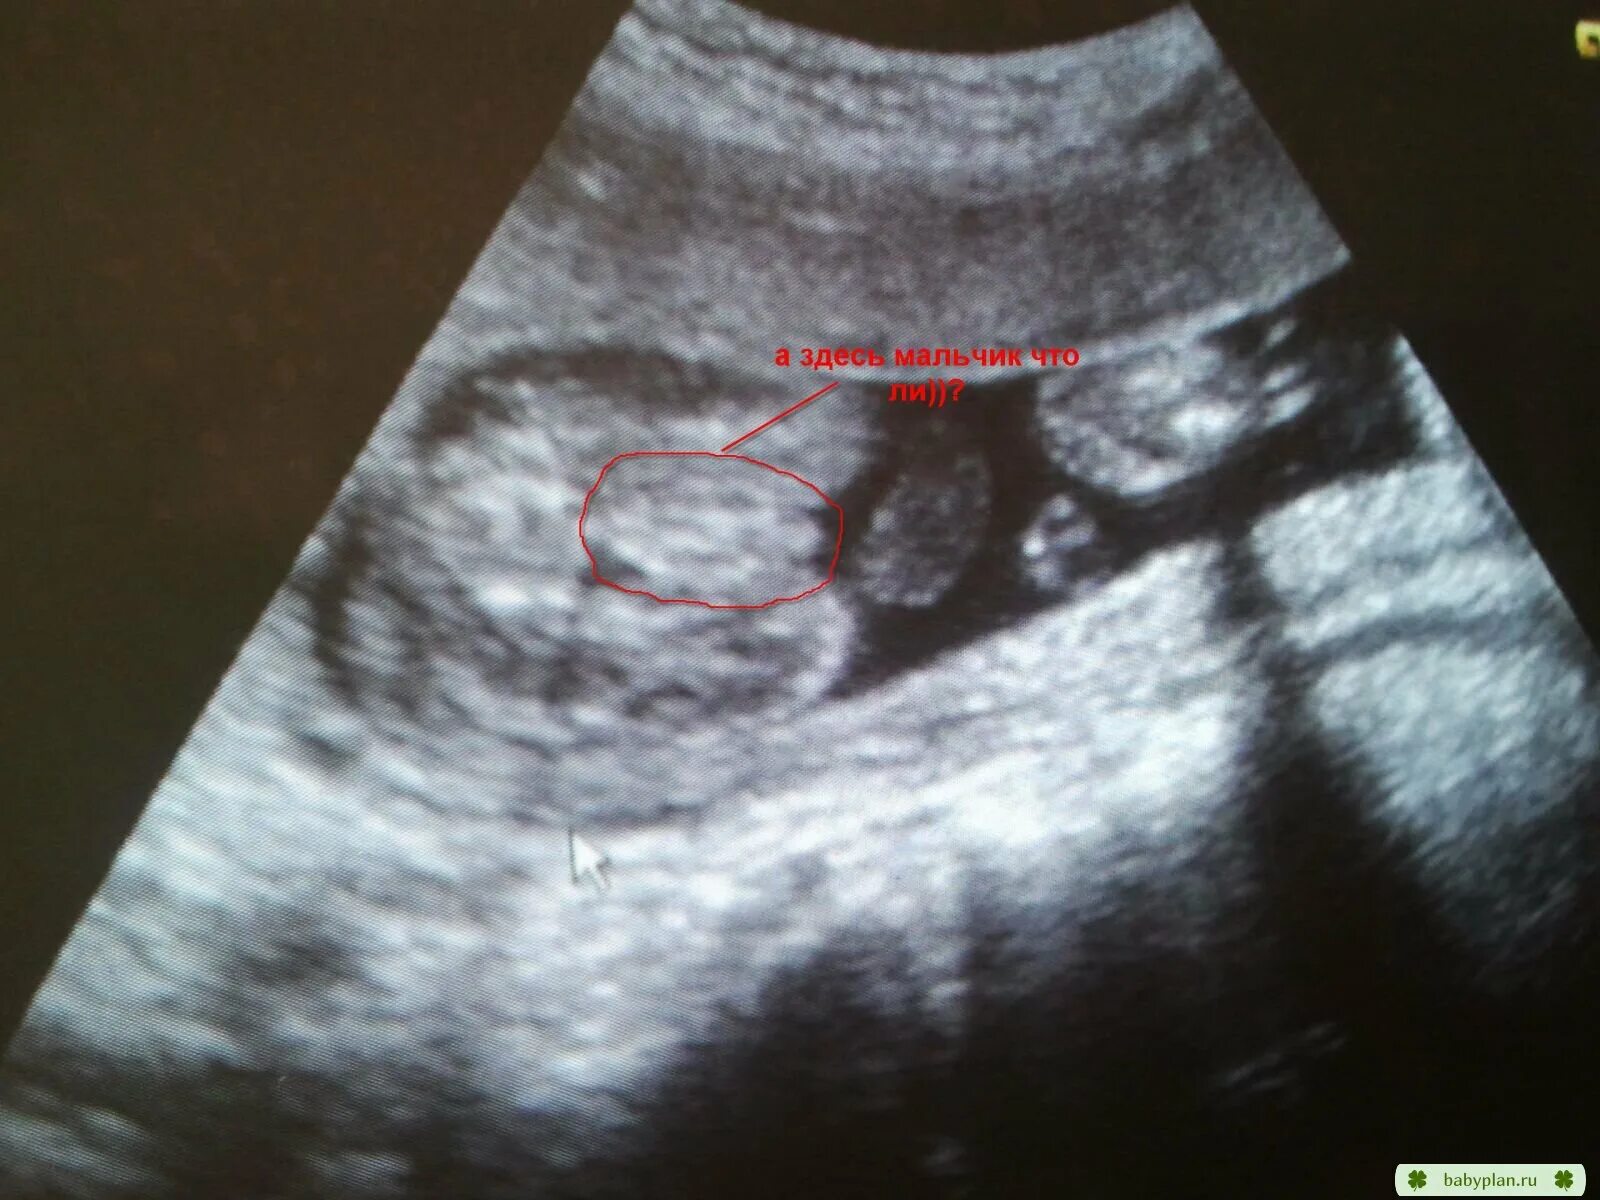

Как определить пол на 20 неделе